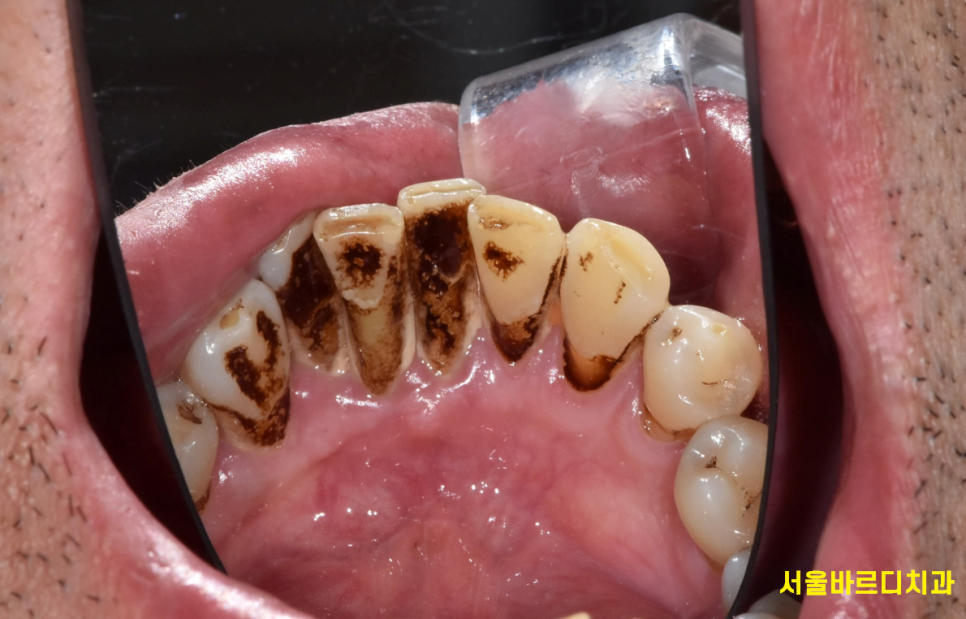

특히 흡연자는 임플란트 실패율이 비흡연자보다 2~3배 높다는 연구 결과도 있고

실제로도 흡연을 많이 하시는 분들이

골 유착이 제대로 되지 않아 임플란트 재수술을 하는 경우가 많습니다.

230620 흡연으로 착색된 치아

금연은 필수!!!!